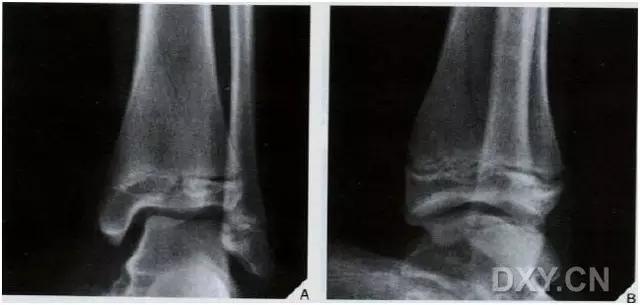

1. 三平面骨折(Triplane fracture )

即累及远端胫骨骨骺的骨折可因骨折线延入其他两个平面而变得复杂,因而称之。骨折由矢状面内的骨骺骨折,经生长板外侧面的轴位面内水平方向骨折,与冠状面内经干骺端到骨干的斜行骨折,自生长板的前侧面伸延至胫骨的后侧皮质。

三平面骨折示意图

图为一 12 岁女孩左踝典型的三平面骨折

三平面骨折 CT 片

三平面骨折 CT 重建